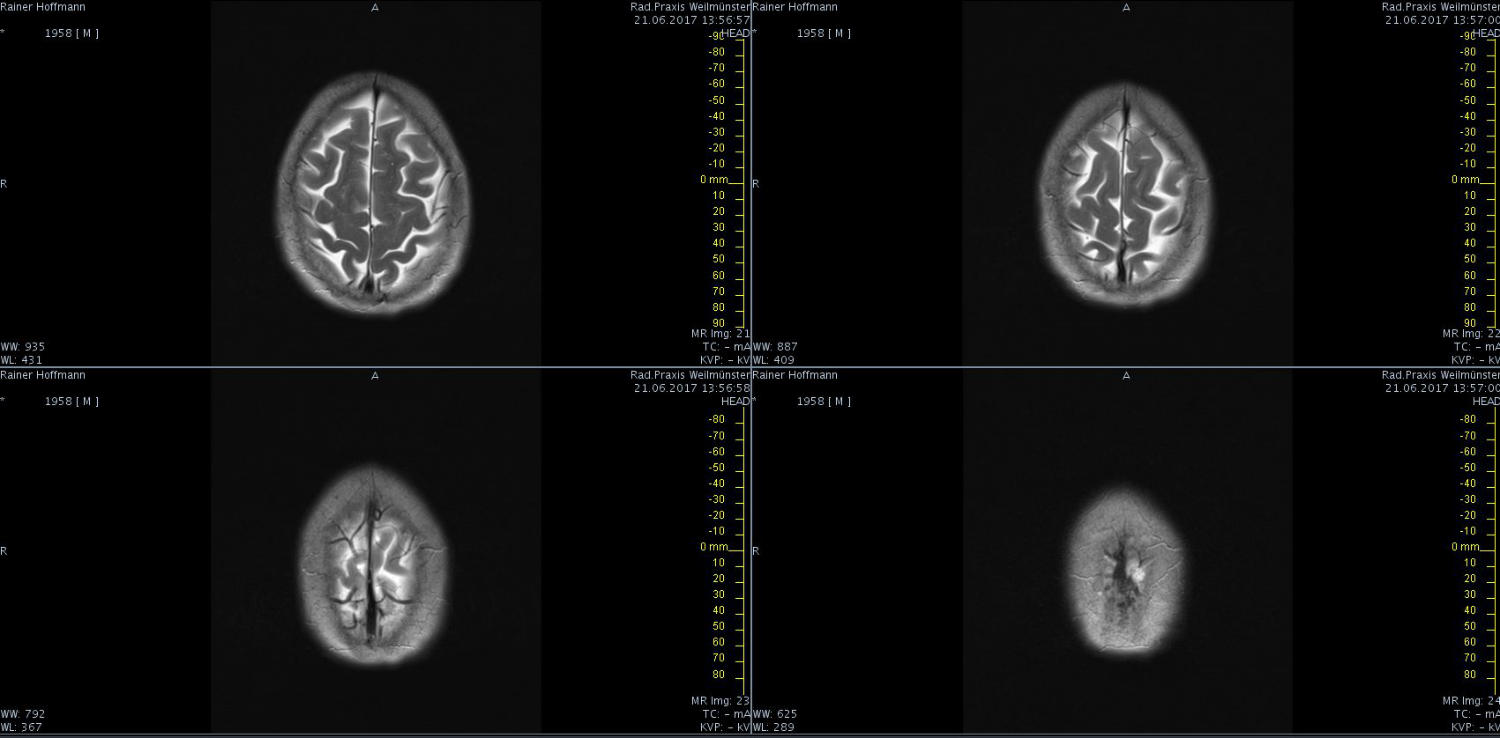

Das ist ja ganz toll, dass Ihr die Seite so schnell gefunden habt. Ich zeige euch jetzt ein ganz, ganz anderes Paßfoto von mir. Es könnte Ähnlichkeiten zu anderen lebenden oder bereits verstorbenen Personen geben. Wenn Ihr das erste Bild oben links anklickt wird es ver- größert dargestellt. Dann kann man mit den Pfeiltasten am unteren Bild- rand durch meinen Kopf blättern. Es gibt nicht viel zu sehen. Vielen Dank an Martina für Ihre Hilfe.

MRT